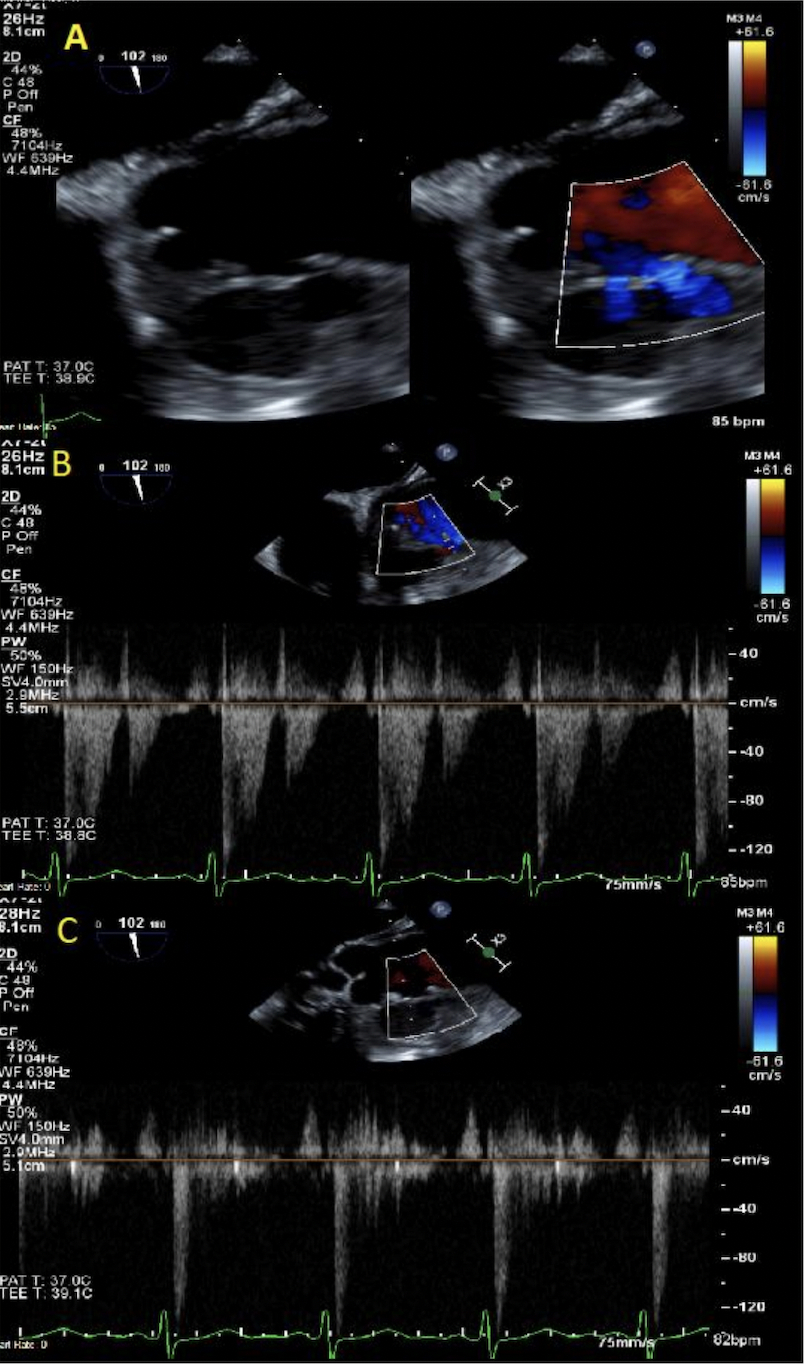

Abstract Body (Do not enter title and authors here): Description of Case: A 57 y.o. male with a hx of prior MSSA bactermia and RCA aneurysm presented for intermittent fevers. His exam showed a harsh systolic murmur at the pulmonic post. ESR and CRP were elevated at 78 mm/hr and 17.1 mg/dL, respectively. WBC of 32.1 x 10e3/uL and a HGB of 8.8 g/dL. Blood cultures were positive for MSSA. Imaging with a CTA Chest, TTE, TEE, and cardiac MRI showed a multilobular 5 x 2.5 x 5.3 cm PSA originating from the proximal ascending aorta.

It is worth noting is the compression of the pseudoaneurysm on the pulmonary artery. This is a very rare complication of ascending aortic pathology. In our patient, pulmonary artery compression was noted on his initial imaging and persistent throughout. However, right heart failure did not develop until his immediate post-operative course, and it’s possible that the necessary shifting of his pseudoaneurysm within his operation contributed to worsening compression on his pulmonary artery and subsequent mortality.